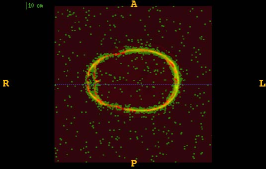

Figure 1 shows the examples of pixel selection masks generated using tested approaches at the highest resolution level for pixel sampling rate 0.5%. It is obvious that the samples generated with the URS approach are extremely spread, whereas the samples generated with the GMS approach are overly concentrated along the gradient magnitude structures present in the image. The proposed approach produces samples that balance those two extremities.